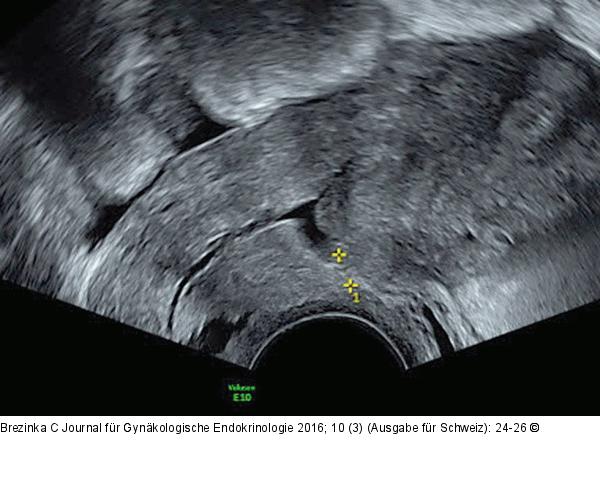

Abbildung 9: Ultraschall-Serometra Sectionarbe mit NaCl als Kontrastmittel. Die residuale myometriale Dicke beträgt 5 mm. |

Sectionarbe mit NaCl als Kontrastmittel. Die residuale myometriale Dicke beträgt 5 mm. |